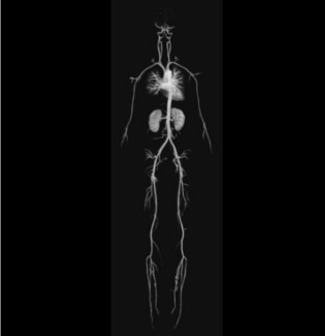

MR Angiography

MR ANGIOGRAPHY